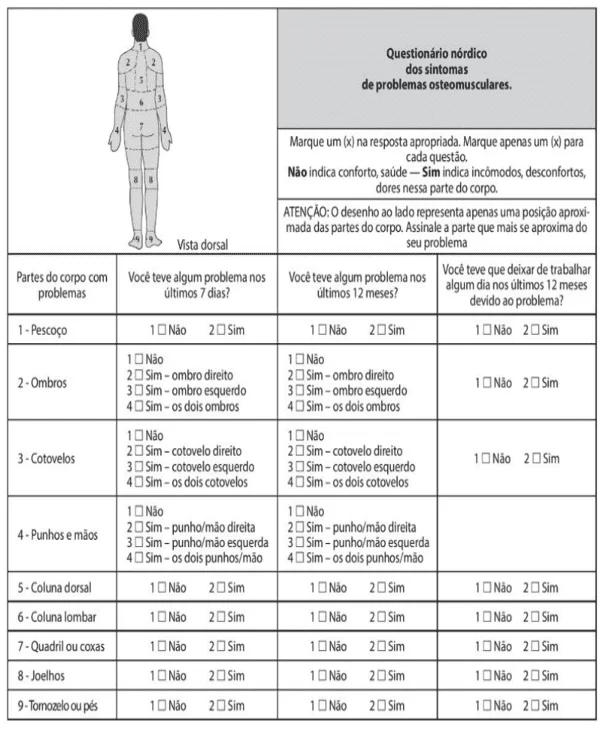

Aplicação do método OWAS e questionário nórdico como ferramenta de adequação ergonômica em uma empresa do ramo alimentício

No segmento da indústria alimentícia, a maior parte dos setores apresenta significativos riscos ergonômicos no curso das jornadas de